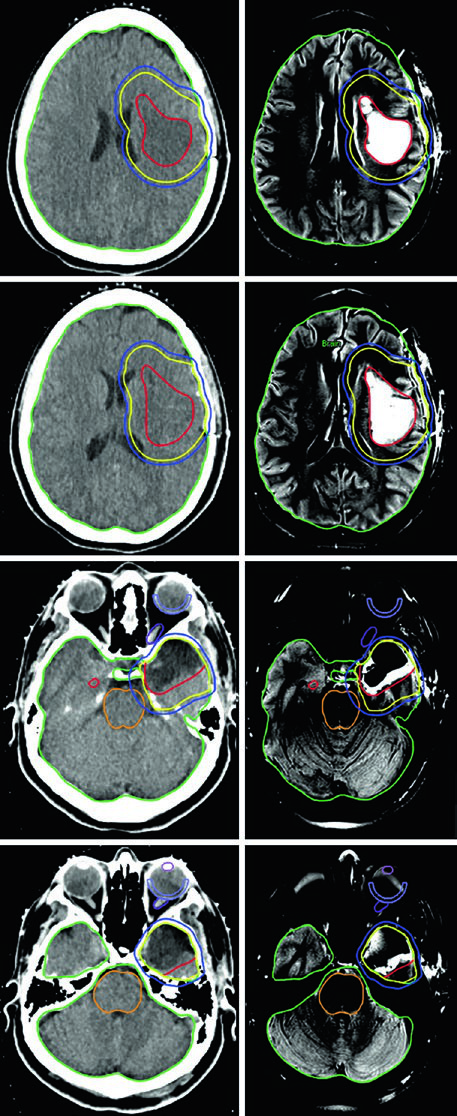

Na prática, o caso do oligodendroglioma ilustrado na Figura 29.5 mostra um paciente após craniotomia frontotemporal esquerda com ressecção parcial. O GTV (vermelho) abrange a doença residual em FLAIR e a cavidade operatória. A expansão de 1,0 cm gera o CTV (amarelo), com restrição anatômica fora da fossa posterior, crânio e estruturas de linha média. O PTV (azul) recebe margem adicional de 0,3 cm.